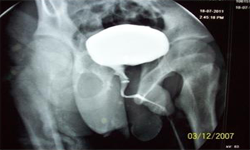

X Ray Showing Deformed Pelvis Scars of Multiple Pelvic Reconstructions

He was evaluated and investigated in detail and planned for artificial urinary sphincter. Preoperatively, micturating cystourethrogram, urodyanmic study, cystoscopy were done. The upper tracts were normal. There was no vesicoureteric reflux, stricture. Bladder capacity was 250 ml, maximum detrussor pressure was 30 cm of water and insignificant residual urine.